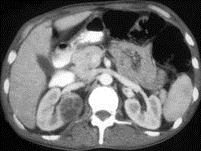

问题 男,35岁,右侧腰部疼痛伴发热,请根据所示图像,选择最可能诊断 ( )

选项 A、右肾转移瘤 B、前列腺脓肿 C、右侧单纯性肾囊肿 D、右侧囊性肾癌 E、右侧肾脓肿

答案 BE